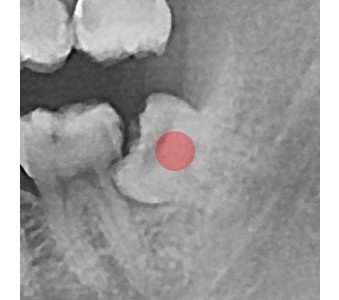

以成果证明实力。

国际摩牙齿科

真实临床案例